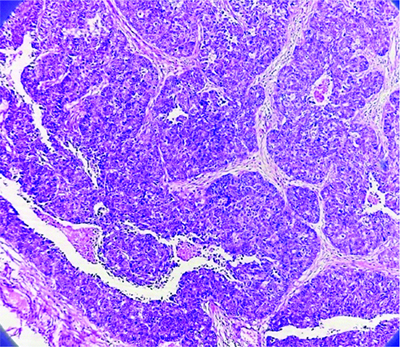

The gross specimen showed a local excision of breast tissue measuring 8×7×4 cm, with a skin flap measuring 6×3 cm [Table/Fig-1]. The cut section revealed a well-circumscribed grey-white to brownish lump with a granular solid cut surface. The adjacent breast tissue displayed patchy grey-white areas. The base margin was 1.5 cm away, while the rest of the resection margins were 1.5, 3, 5, and 3 cm away [Table/Fig-2]. Microscopically, the tumour was well-circumscribed, consisting of a central sclerotic area and solid nodules comprised of sheets of cells separated by fibrovascular septae [Table/Fig-3]. The cells had enlarged, pleomorphic, hyperchromatic, mitotically active nuclei with clumped chromatin and moderate eosinophilic cytoplasm. The adjacent breast tissue showed Lobular Carcinoma in-situ (LCIS) and focal invasion, with no lymphovascular emboli or perineural invasion [Table/Fig-4].

Low magnification microscopic picture of Solid Papillary Carcinoma (SPC) breast- A well-circumscribed tumour with solid nodules and a core sclerotic region is observed under a microscope. The cells exhibit larger, pleomorphic hyperchromatic nuclei with clumped chromatin and mild eosinophilic cytoplasm (4x).

Low Magnification (4x) of Solid Papillary Carcinoma (SPC) - A well-circumscribed tumour in breast tissue was seen under a microscope. It had solid nodules without lympho-vascular emboli or perineural invasion, and a central sclerotic region. Arrows are marked at areas of invasion. (Images from left to right)